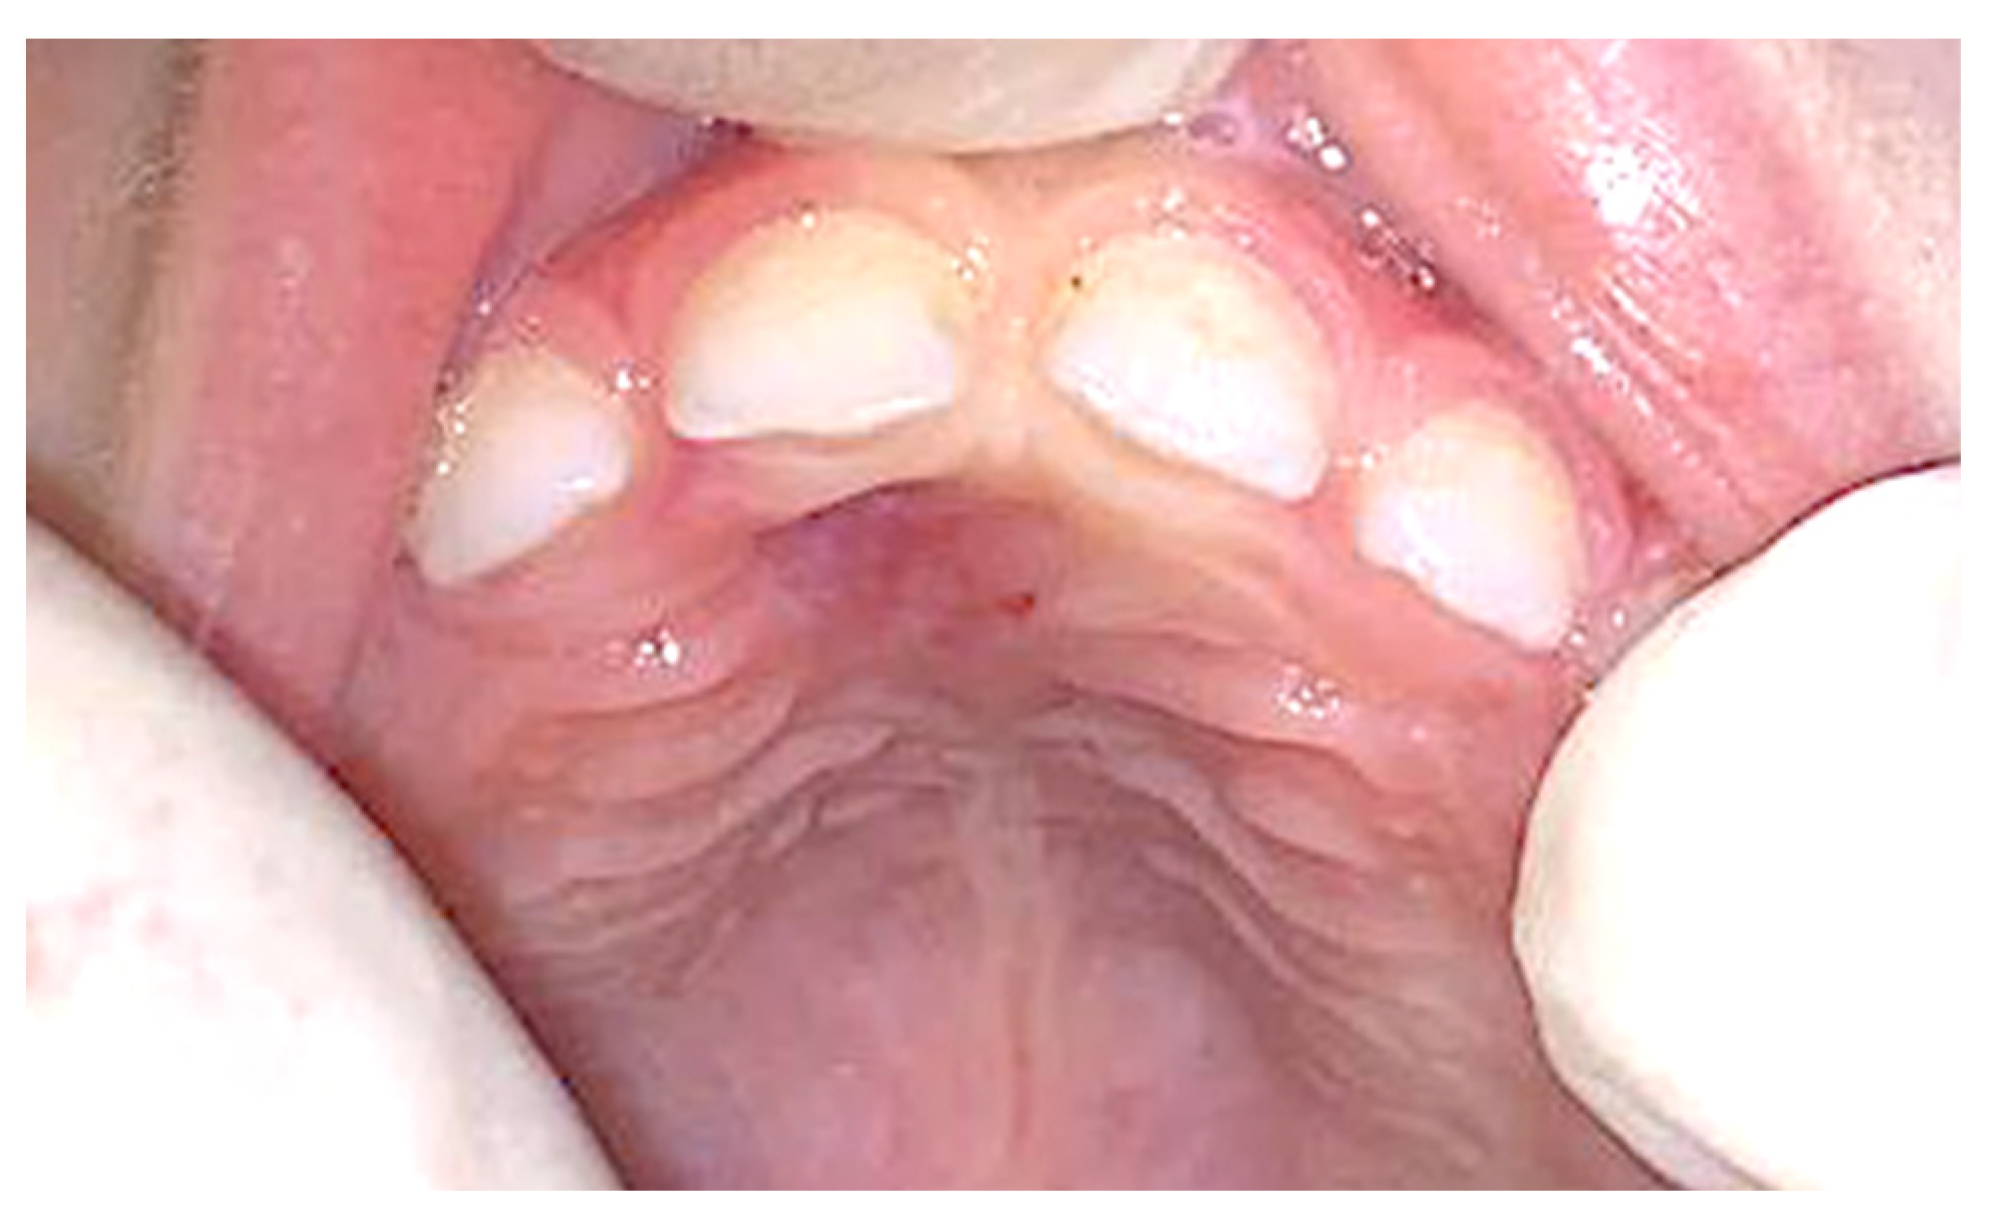

2. Case Presentation

| 19 | This study (2023) | Male/4 years | Maxilla, palatal region | Peripheral ossifying fibroma | Peripheral developing odontoma | Surgical laser excision |